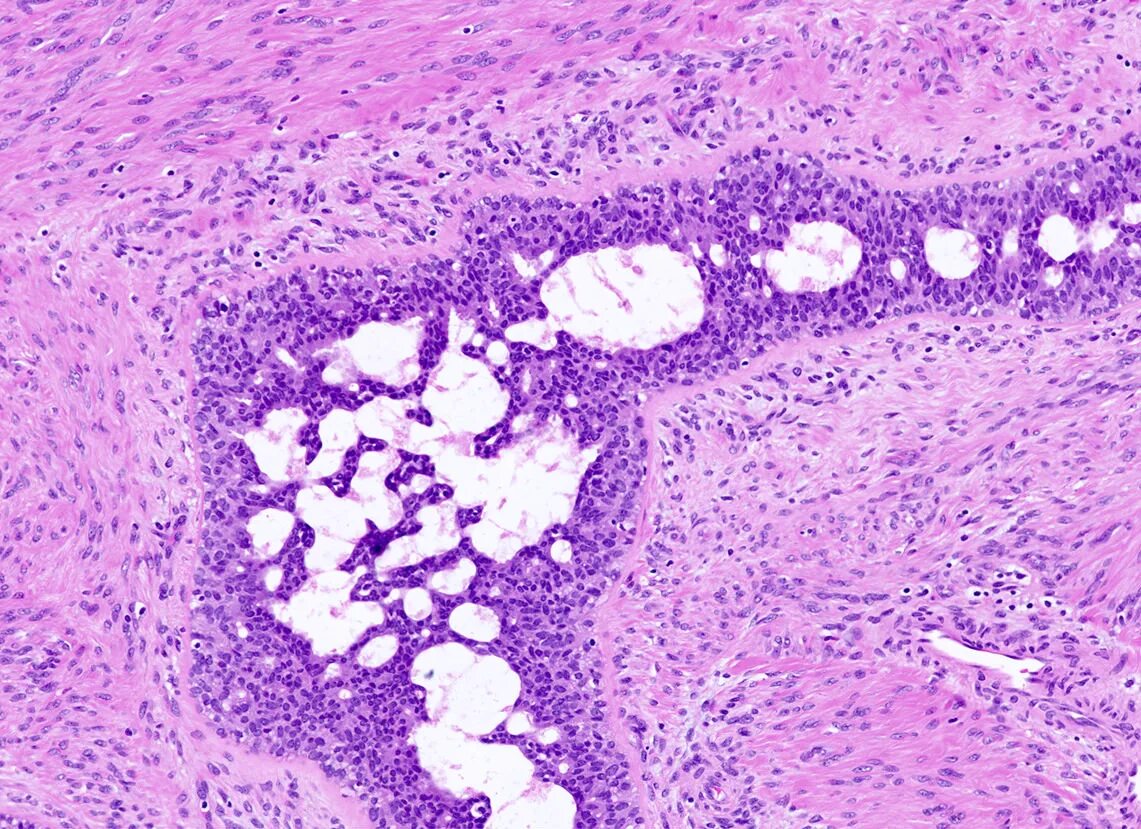

Фиброаденома гистология